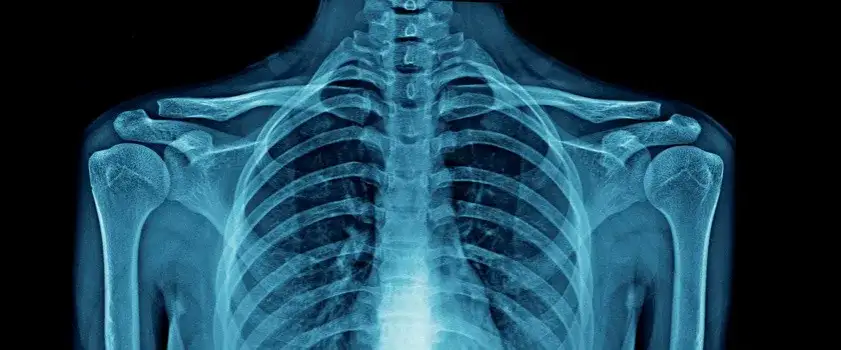

- Diagnostyka opiera się na badaniach obrazowych, takich jak RTG.

Diagnostyka sklerotyzacji - jak wygląda proces oceny stanu stawów?

Diagnostyka sklerotyzacji opiera się na badaniach obrazowych, takich jak zdjęcia rentgenowskie (RTG). Te metody pozwalają zidentyfikować zwiększoną gęstość kości podchrzęstnej oraz inne zmiany patologiczne. Dokładna ocena stanu stawów jest kluczowa dla zaplanowania dalszego leczenia.

Badania obrazowe są niezwykle istotne, ponieważ umożliwiają określenie stopnia sklerotyzacji oraz innych powiązanych problemów, co pozwala lekarzom na podejmowanie świadomych decyzji terapeutycznych.